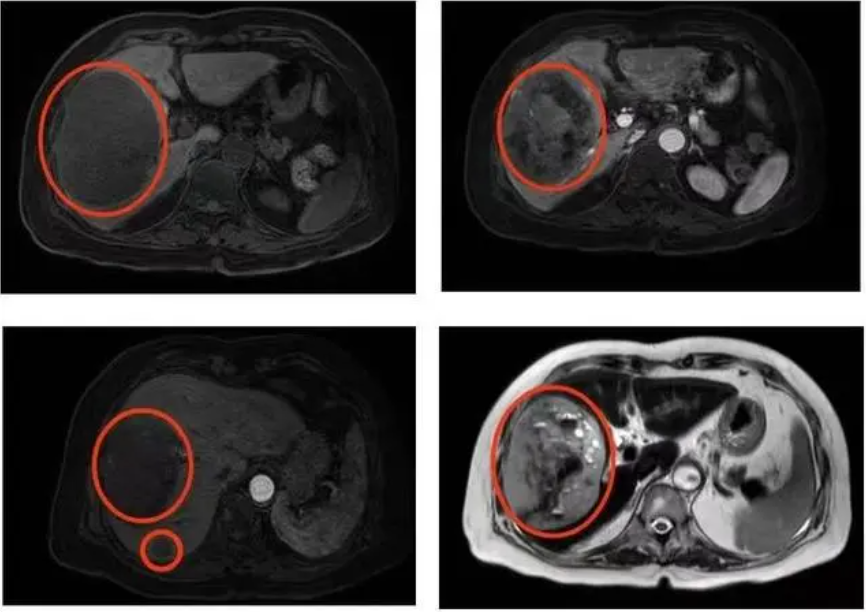

入院后,普外科迅速完善各项检查,MRI平扫+增强提示,肝右叶占位性病变11cmx10.6cmx7.6cm,怀疑其性质为恶性肿瘤。结合周奶奶病史、症状体征及相关辅助检查结果,考虑胃肠道间质瘤肝转移可能性大,而手术是唯一可能有治愈机会的方法。

图示为肿瘤位置及大小